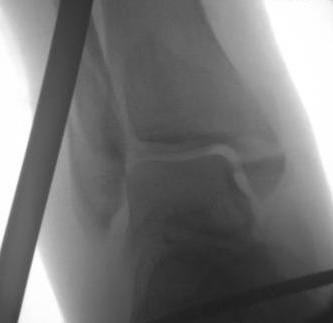

Ankle dislocation

Reduction under conscious sedation

- protects skin medially

- conscious sedation in emergency department

- well moulded cast

- unstable ankles need monitoring for loss of reduction

- can need external fixation to maintain position

Dislocationdislocationdislocation